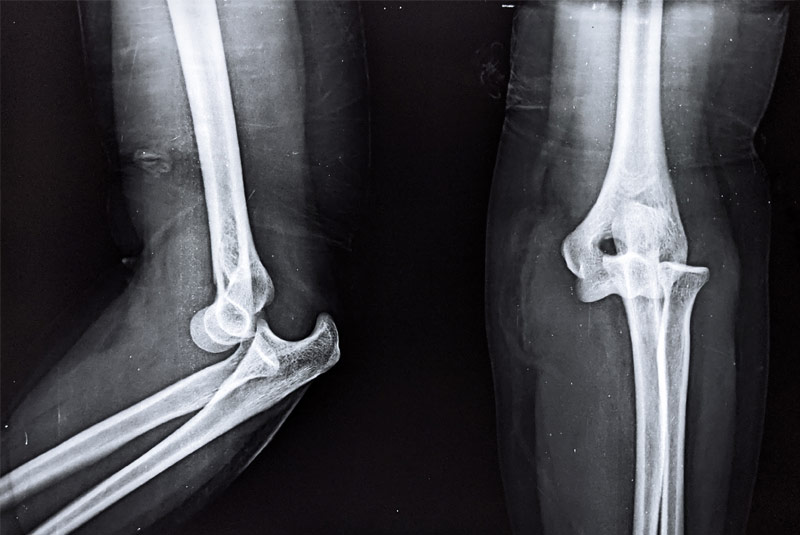

• Elbow Fracture Fixation